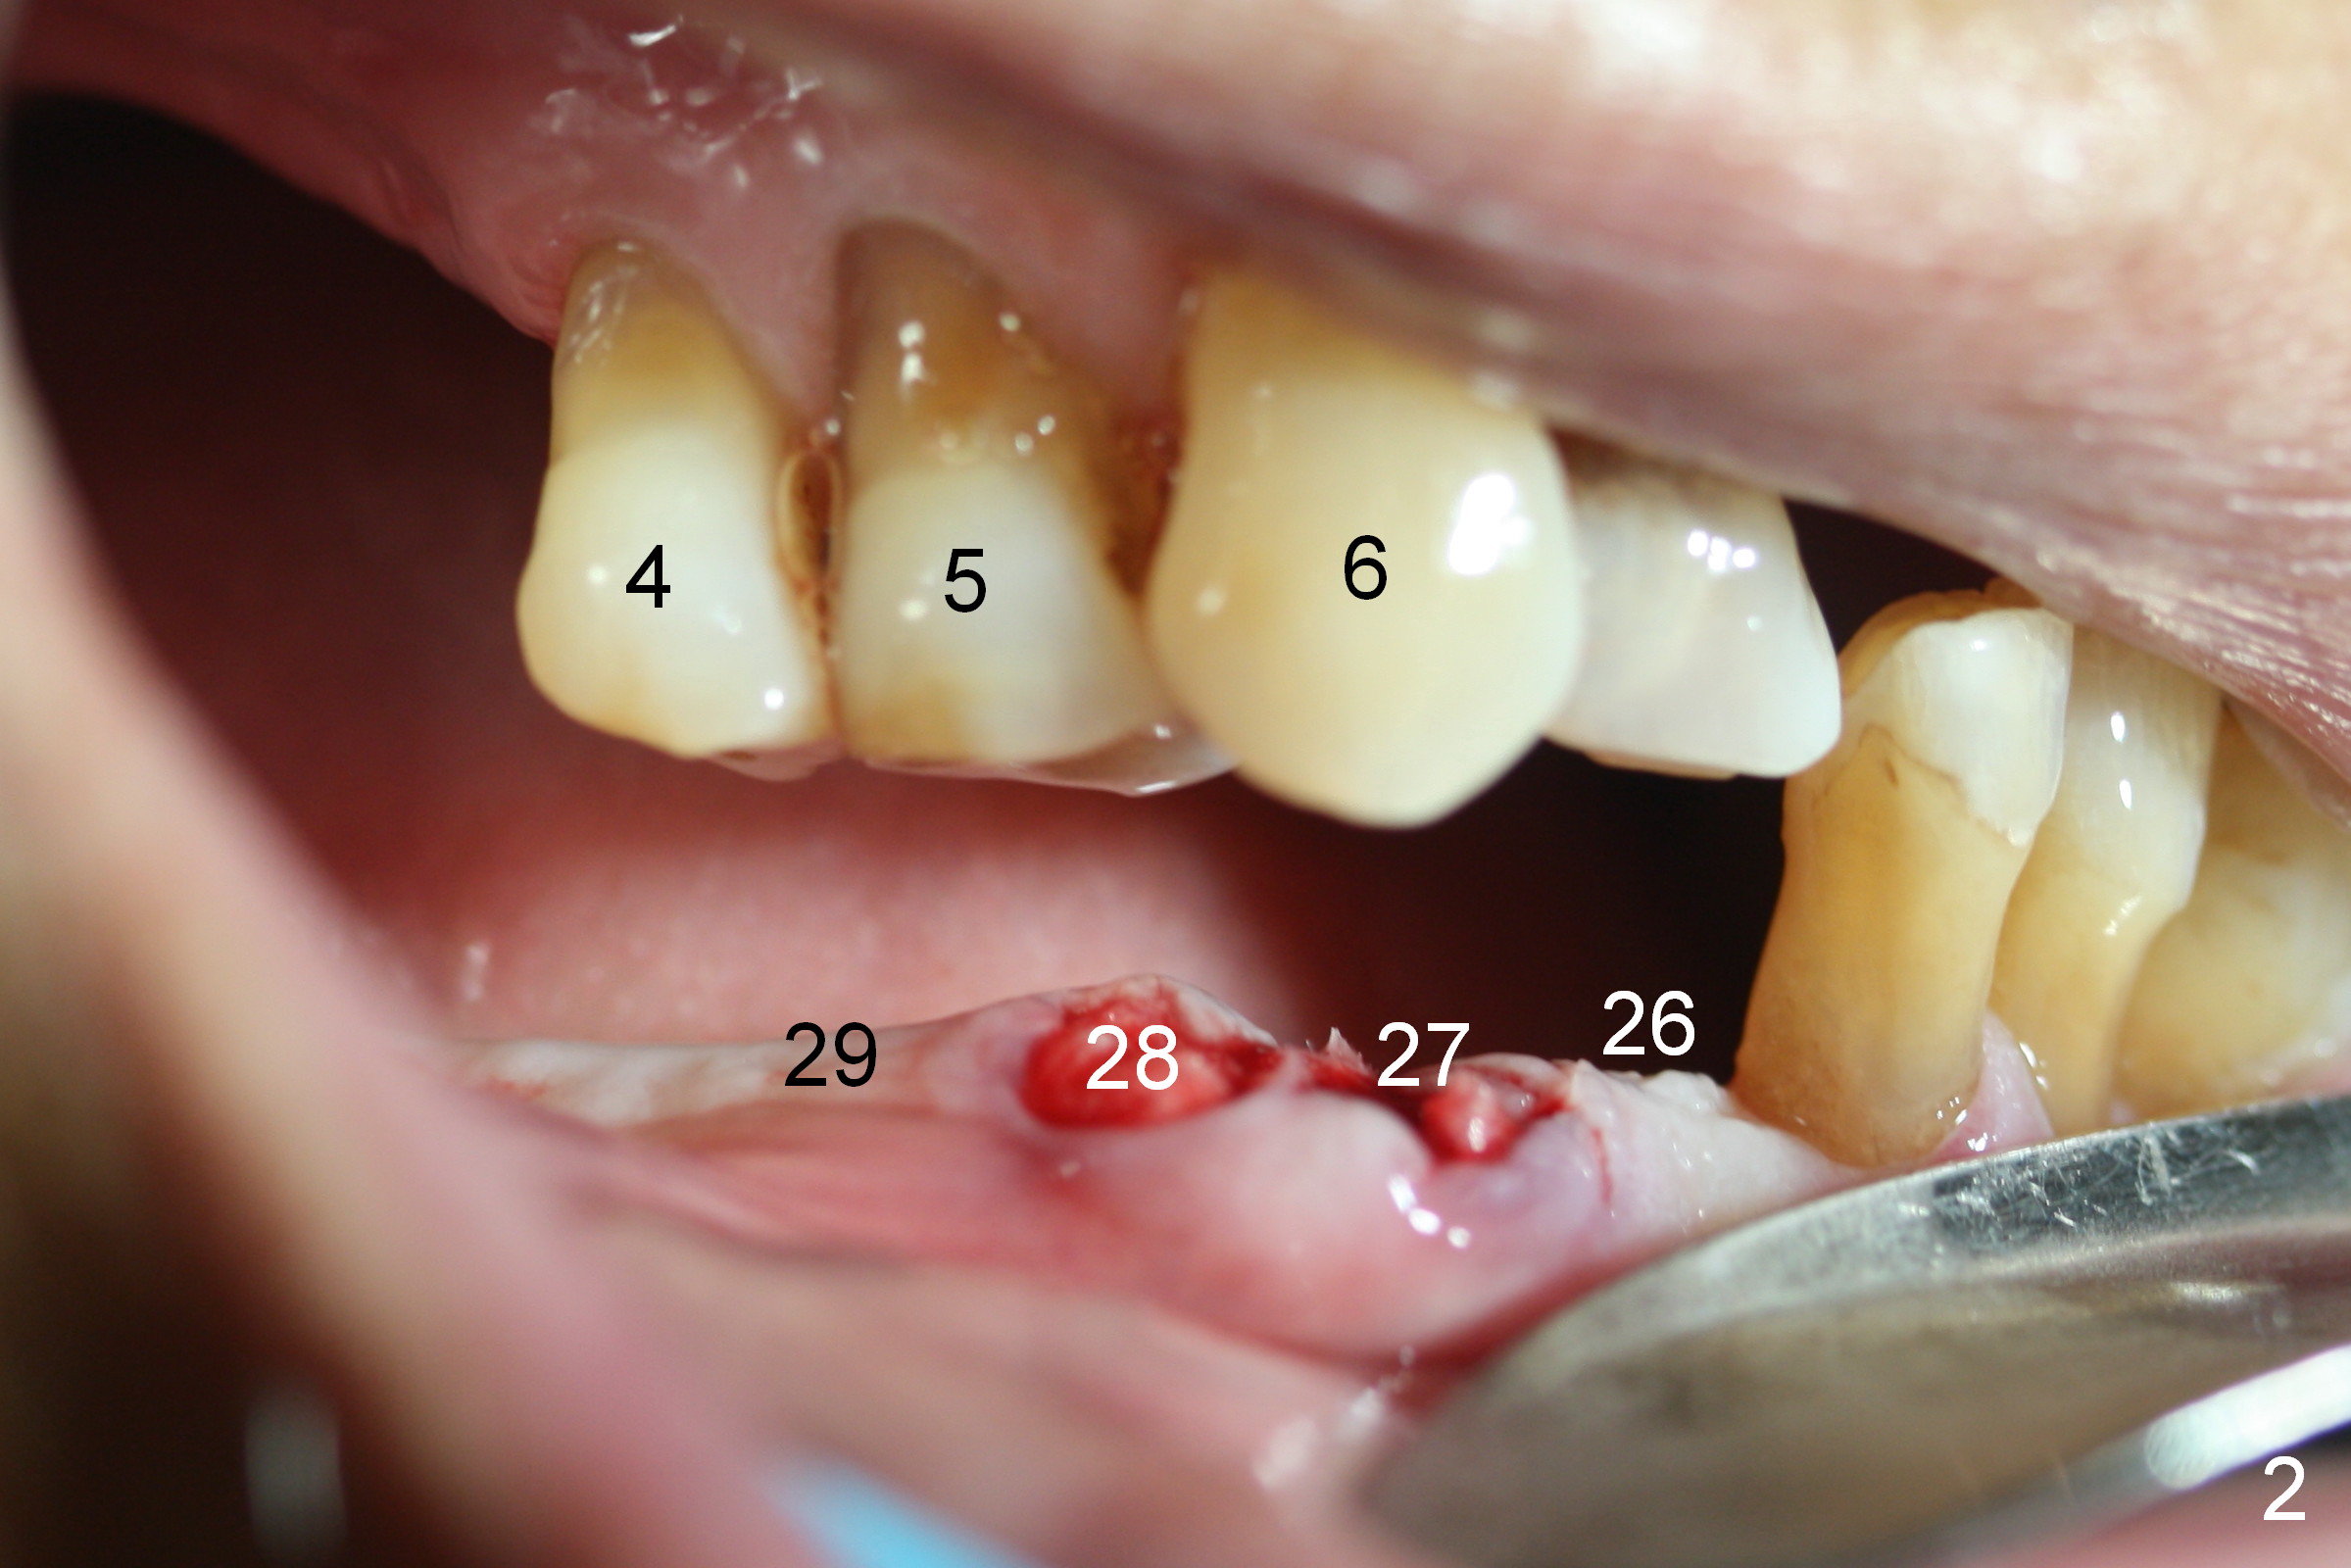

A 86-year-old man returns to office for the lower right quadrant reconstruction with implants. In addition to the immediate ones at the sites of #27 and 28 (Fig.1), how many and where else? The patient reveals that he does not plan to get an implant at the site of #3 (Fig.2). Therefore there is no need for an implant at #30. Preop CT shows that bone width is compromised at #26. So the 3rd site will be #29 (Fig.3,4). All of the 3 implants (4.5x14 mm, 4.5x12, and 4.1x12 mm) achieve primary stability (»55 Ncm). An immediate provisional could be provided, but it seems difficult to close the buccal (Fig.5 B) gaps of #27 and 28 after bone graft with the provisional. In contrast, the gingiva adapts to the implant at #29 well (Fig.6 B). Perio dressing is applied to the abutments (Fig. 7: #27-29), the edentulous space at #26 and the neighboring teeth (#23,24). It would be ideal to apply a non-resorbable membrane to the buccal opening at #27,28 (Fig.8 white line) prior to perio dressing placement. In case of dislodgement of the latter, the membrane is able to keep bone graft in place.